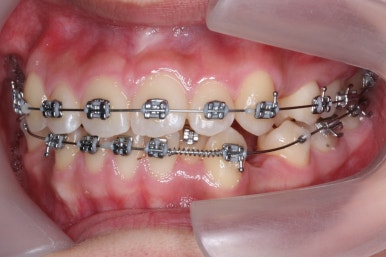

부산교정전문의 키다리아저씨치과에 처음 내원하셨을 때 당시의 입안 모습입니다.

윗니 뿐만 아니라 아랫니 부위에도 덧니가 관찰됩니다. 다른 앞니, 어금니 부위도 약간 삐뚤한 부분이 보입니다.